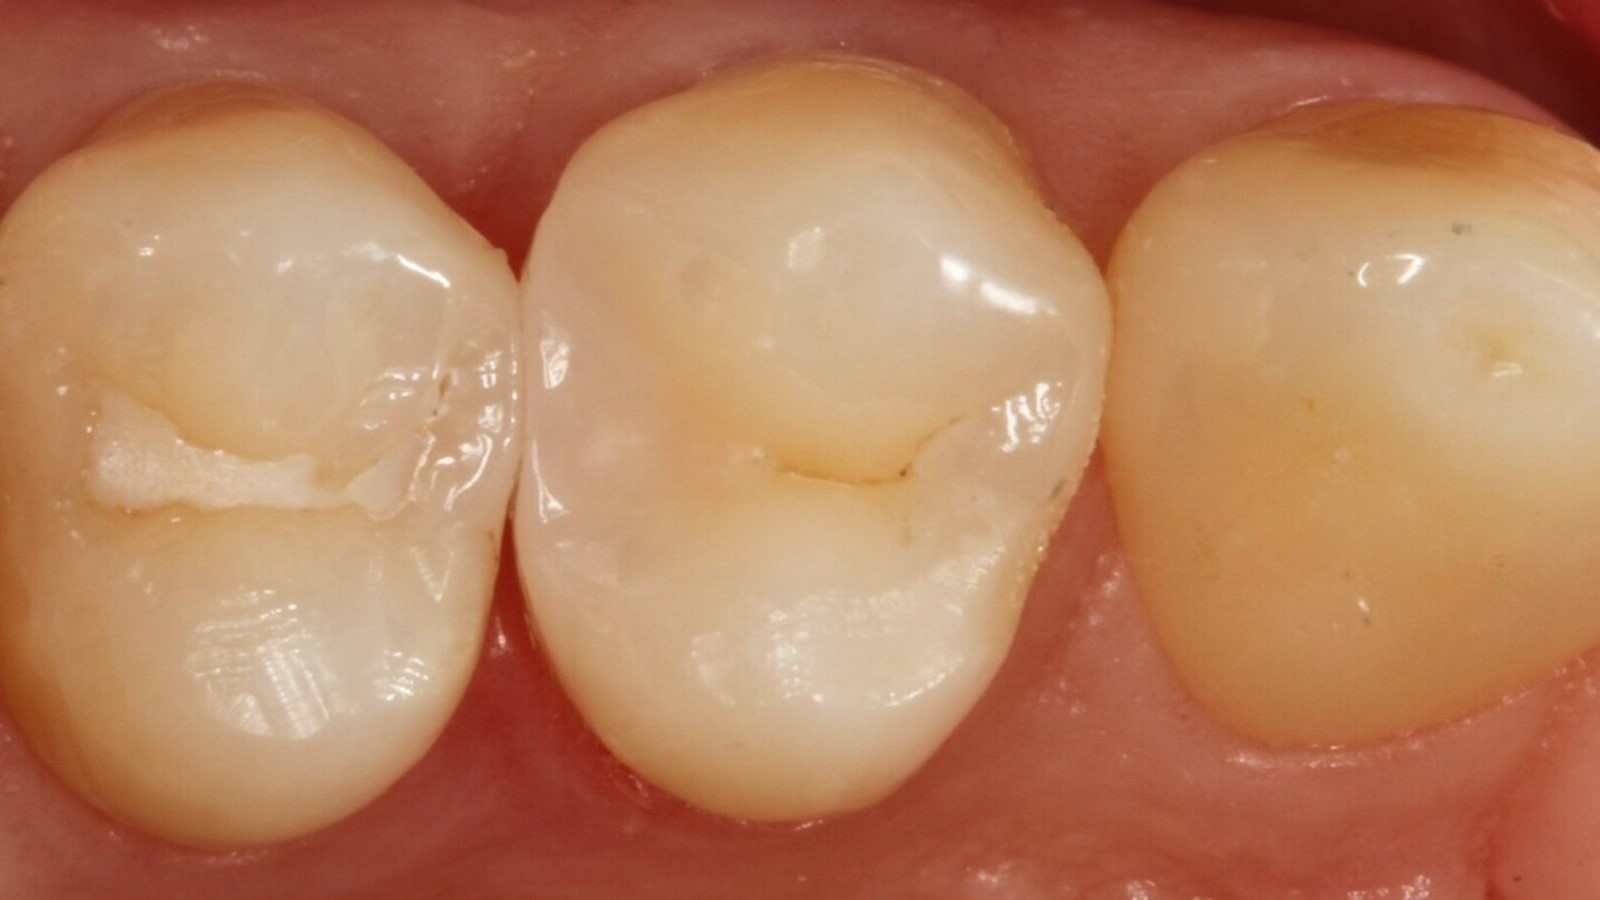

Le professeur Ernst a d'abord identifié les caries non visibles et a ouvert la lésion carieuse pour montrer le problème au patient (Fig. 1-2). Il a ensuite excavé la carie, préparé la cavité et placé une matrice sectionnelle (Fig. 3) avant de sceller la cavité avec de l'adhésif (Fig. 4). En une seule étape, il a rempli la cavité avec Venus Bulk Flow ONE (Fig. 5). Une fois la restauration terminée, le Pr Ernst l'a polie (Fig. 6) et a pris une radiographie de contrôle, qui montre également l'excellente radiopacité de Venus Bulk Flow ONE (Fig. 7).